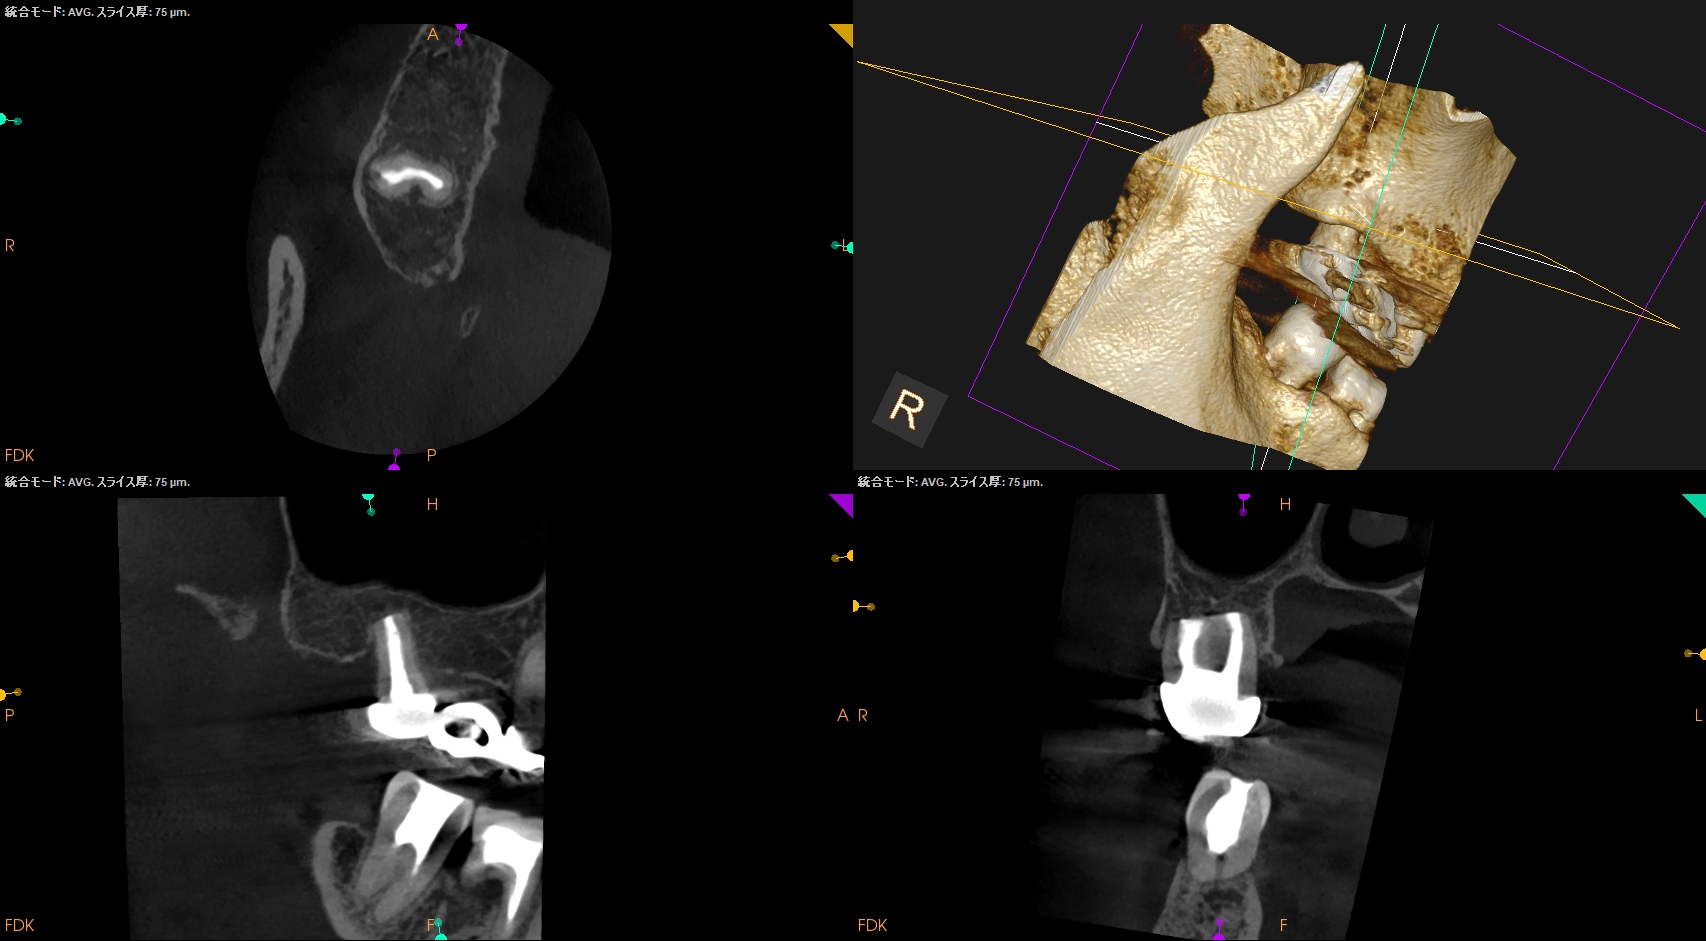

Intentional Replantationから7年が経過していた。

#2 Intentional Replantation 7yr recall(2025.12.9)

問題はない。